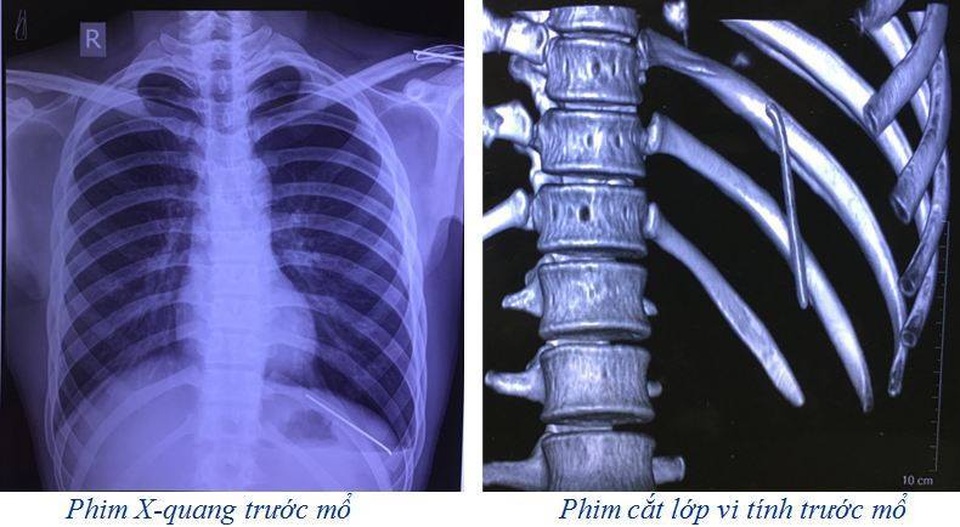

Sau khi tiến hành nội soi dạ dày tá tràng, không tìm thấy di vật, các bác sĩ đã chụp cắt lớp vi tính lồng ngực, phát hiện dị vật kim khí trong khoang màng phổi trái kèm theo tràn khí.

Tại BV Đa khoa Phú Thọ, bệnh nhân được chỉ định phẫu thuật nội soi ngực trái để lấy di vật và xử lý tràn khí khoang màng phổi trái. Sau phẫu thuật 1 ngày, người bệnh ổn định, đã được rút bỏ dẫn lưu khoang màng phổi, đi lại và ăn uống gần như bình thường.

Nguyên nhân là do chiếc đinh đã di chuyển từ vị trí xương đòn trái. Theo thời gian chiếc đinh rơi tự do vào trong khoang màng phổi trái.

Được biết, trước khi mổ ca bệnh này thì kíp phẫu thuật và kíp gây mê hồi sức đã chuẩn bị tối đa các phương án đề phòng nếu có tổn thương hệ thống mạch máu lớn và tim. Rất may mắn là chiếc đinh chỉ làm rách nhu mô phổi gây tràn khí khoang màng phổi trái.